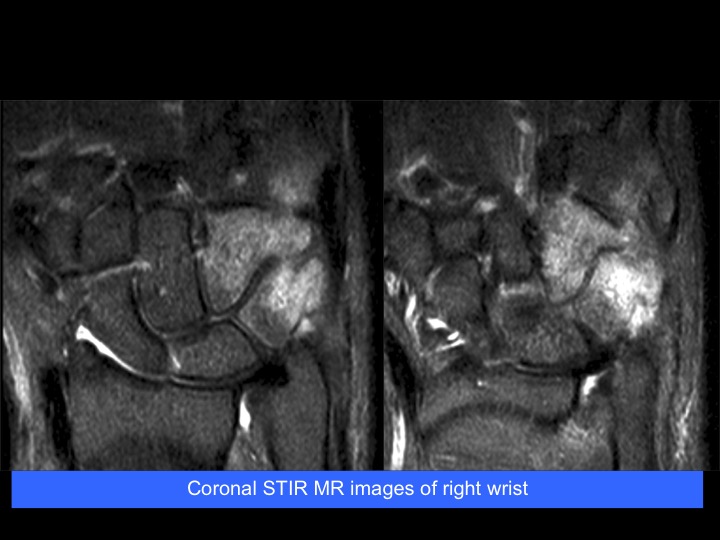

32-year-old man with pain and swelling on ulnar wrist and hand

Trevors Disease (Dysplasia Ephiphysealis Hemimelica)

Uncommon skeletal developmental disorder which usually affects the lower limb, with only rare reports of upper limb involvement. DEH most commonly affects the ankle or hindfoot and is more commonly unilateral, medial or lateral (hemimelica). Reference article.